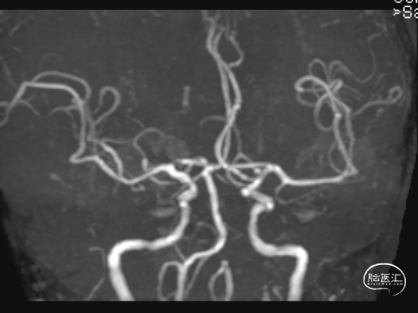

头颈CTA:左侧椎动脉起始、左侧锁骨下动脉重度狭窄。

术后头晕呕吐,当日DWI:左侧小脑梗死,MRA未见明显大血管栓塞。

术后第3天患者恶心、呕吐症状消失,仍有头晕,复查DWI及MRA。